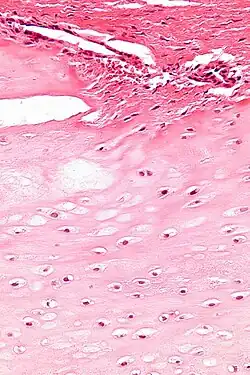

Makroskopisch handelt es sich in den meisten Fällen um grau-blaue Tumorknoten, die in der Regel unter drei Zentimeter groß und lobuliert sind. Diese liegen in der Regel im Markraum der langen Röhrenknochen. Histologisch handelt es sich bei Enchondromen um reifes Knorpelgewebe mit Knorpel-typischer hyaliner Matrix und histologisch gutartigen Knorpelzellen (Chondrozyten). Im Tumorrand findet sich in der Regel eine enchondrale Ossifikation. Auch das Tumorzentrum kann nach Nekrose verkalken. Das umgebende Knochengewebe wird in der Regel verdrängt, aber nicht zerstört.